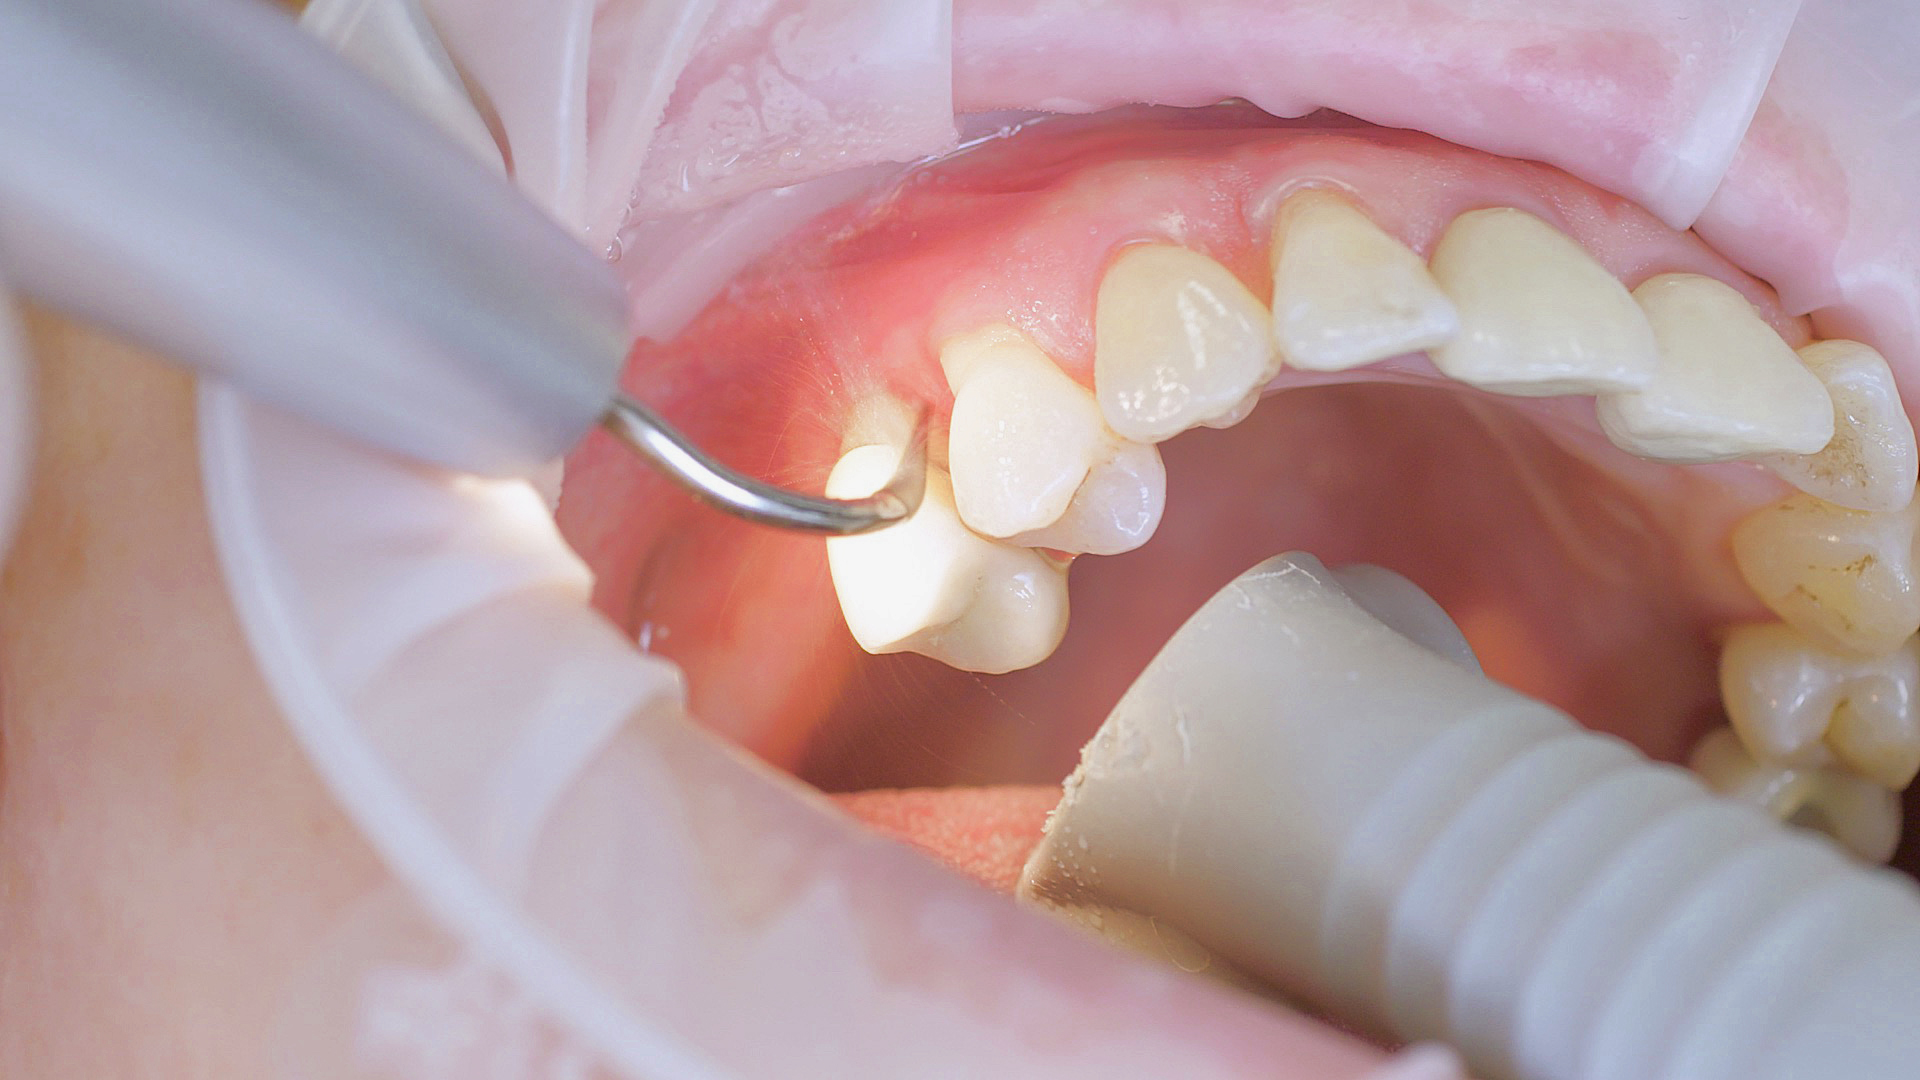

Every dental examination is based on a detailed medical history combined with targeted diagnostics con- taining as much detail as possible: The dentist records systemic risk factors such as diabetes or smoking and identifies any potential increased tendency to inflammation.[3] Hard and soft tissues are examined and periodontal pockets are probed in a screening test according to PSR (Periodontal Screening and Recording). In case of abnormal findings, the periodontal status is then re- corded and therapy is initiated where necessary. This treatment begins with professional biofilm management, by using, for example, rotary cups and polishing com pounds (Fig. 1), and comprehensive instructions in oral hygiene. Sonic or ultrasonic systems remain an effective alternative or supplement to manual instruments for sub- gingival debridement and biofilm management (presentation by Prof. Dr Ulrich Schlagenhauf; Fig. 2). Supplementary use of photodynamic therapy, air polishing or local and systemic antibiotics is not adequately documented (Prof. Dr Sema Hakki).[4] According to Dr Sergio Bizzarro, improved biomarker diagnostics may lead to an increase in customised patient therapy in the future.

Fig. 2: An air scaler efficiently performs the initial debridement, as part of initial periodontal therapy.